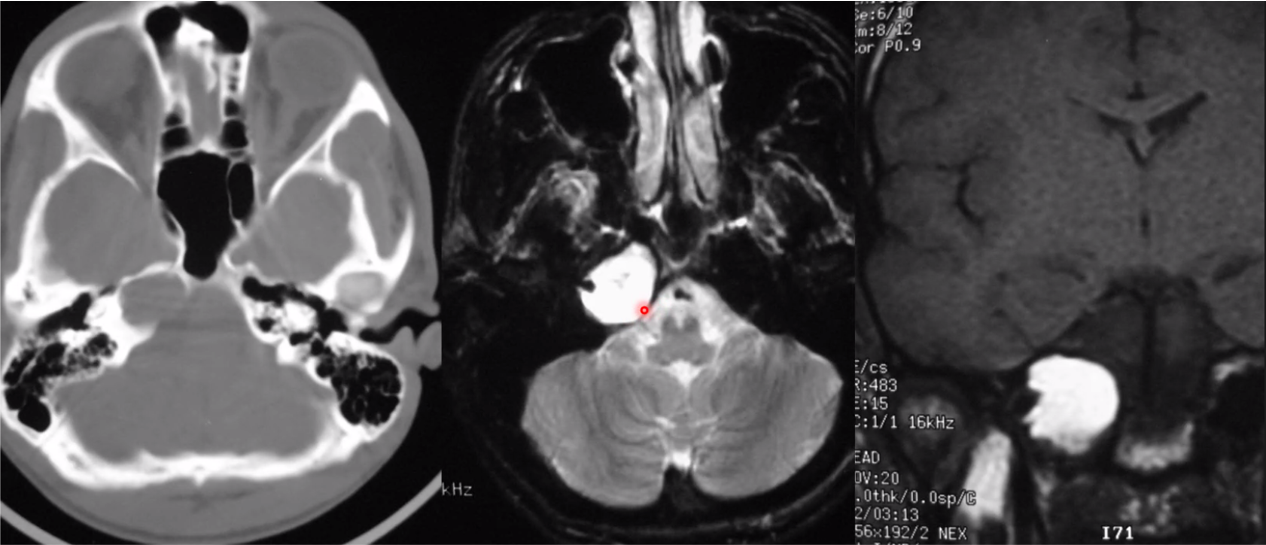

vein of galen malformation